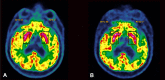

Case report: A 90-year-old male developed left hemichorea-hemiballismus after his second dose of the Pfizer-BioNTech COVID-19 vaccine. A wide range of investigations including magnetic resonance imaging did not reveal an alternative cause. [18F]-fluorodeoxyglucose-positron emission tomography (FDG-PET) showed increases in right putamen fixation compared to the left side. The patient showed significant improvement after five days of intravenous corticosteroids, with a normal FDG-PET.

Discussion: This hemichorea-hemiballismus case shows dynamic restoration of putamen metabolism mirroring clinical evolution after administration of corticosteroids, suggesting an autoimmune COVID-19 vaccine-induced reaction.